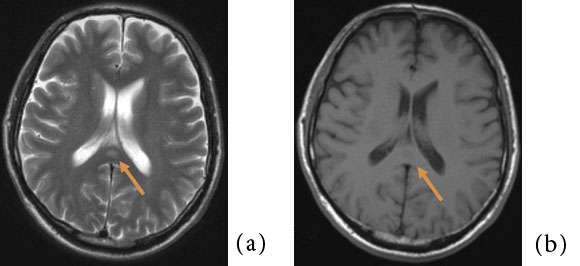

MRI では、T2 強調像および拡散強調像にて 脳梁膨大部中間層に円形もしくは卵円形の高信 号を呈する領域を認め、T1 強調像にて淡い低信 号もしくは等信号を呈する(Fig.1)。ADC map では一過性病変であるにも関わらず、急性期脳 梗塞など細胞障害性変化を来す疾患と同様に病 変部のADC 値は低下している。よって同じ一 過性病変である、高血圧脳症などいわゆるposterior reversible encephalopathy syndrome (PRES)や、高地脳症などにおける血管原性浮 腫とは異なる病態が存在する。このADC 値低 下の原因については軸索の表面を覆うミエリン 鞘の分離によって生じる軸索内浮腫2)が最も考 えられているが、まだコンセンサスは得られて いない。Takanashi らはMERS 患者に共通して 低ナトリウム血症を認めたと報告しており3)、 特に感染症においては嘔吐や下痢に伴う電解質バランスの破綻も関与している可能性がある4)。 異常信号は脳梁の他の部位や、白質に左右対称 性に及ぶこともある。通常は可逆性だが、時に 不可逆性の場合もある。造影MRI にて造影増強効果は認めない1) 5)

Fig.1 50 歳代、男性。軽度の意識レベル低下を認めたためにMRI が施行された。

(e):造影MRI にて同病変に有意な 異常信号は認められない。

(f):10 日後の拡散強調像。脳梁膨 大部に認められた病変は消失。 特に無治療にて症状は軽快した。